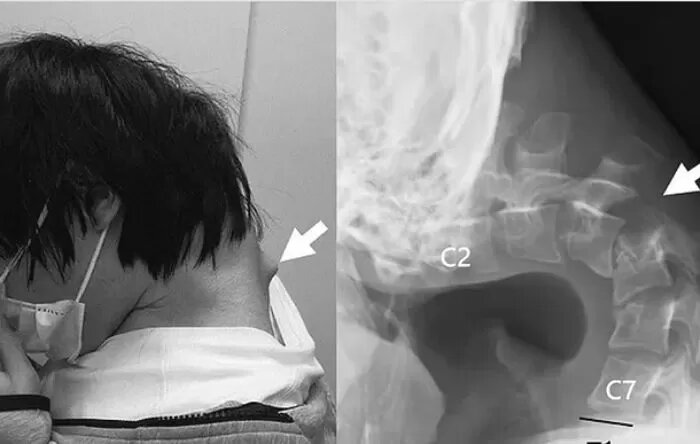

У 25-летнего японца, который большую часть времени проводил, уткнувшись в телефон, в конце концов развилась неспособность поднимать голову, и ему поставили диагноз «синдром опущенной головы». В редком отчёте о случае, опубликованном пару лет назад в медицинском журнале JOS Case Reports, подробно описаны тревожные последствия многочасового наклона головы в течение длительного времени. У пациента, 25-летнего японца, который большую часть времени проводил за играми на телефоне, на задней стороне шеи образовалась большая выпуклость, и он больше не мог поднимать голову, напрягая мышцы шеи. Сообщается, что до обращения за медицинской помощью мужчина испытывал сильные боли в шее и трудности с глотанием пищи, из-за чего он быстро похудел. В конце концов, из-за неестественного положения шея ослабла настолько, что он не мог поднять голову. Японские врачи отметили, что пациент был очень активным ребёнком, но всё изменилось в подростковом возрасте, когда он стал объектом «серьёзных издевательств»

Японские врачи отметили, что пациент был очень активным ребёнком, но всё изменилось в подростковом возрасте, когда он стал объектом «серьёзных издевательств» в школе, из-за чего ему пришлось бросить учёбу и проводить большую часть времени в одиночестве, запершись в своей комнате и играя в телефон. Из-за того, что он часами сидел, склонив голову и глядя в телефон, на задней стороне его шеи образовалась огромная выпуклость. Сканирование показало, что позвонки его шеи были деформированы и смещены, а на верхнем отделе позвоночника образовалась рубцовая ткань из-за того, что он был «чрезмерно вытянут» в течение длительного времени. Сначала врачи пытались лечить его опущенную голову с помощью воротников, но после того, как пациент пожаловался на онемение в шее, они решили выбрать другое решение. В ходе серии хирургических операций они удалили небольшую часть деформированных позвонков и рубцовую ткань, а затем вставили винты и металлические стержни в кости его шеи, чтобы исправить осанку.